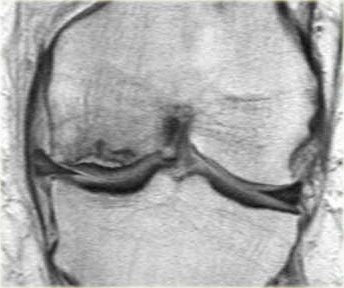

Hãy quan sát hình ảnh bên trái và cố gắng xác định vấn đề của sụn chêm này là gì.

Như bạn đã đoán được qua tiêu đề của đoạn này, đây là một trường hợp sụn chêm lật (flipped meniscus).

Sụn chêm lật là một dạng đặc biệt của rách dạng quai xô (bucket-handle tear).

Sụn chêm lật xảy ra khi mảnh vỡ của sừng sau bị lật ra phía trước, khiến sừng trước của sụn chêm có vẻ to hơn bình thường.

Trên hình ảnh mặt phẳng coronal, trước tiên sẽ thấy sừng trước to và phồng lên.

Ở phía sau sẽ thấy sừng sau rất nhỏ.